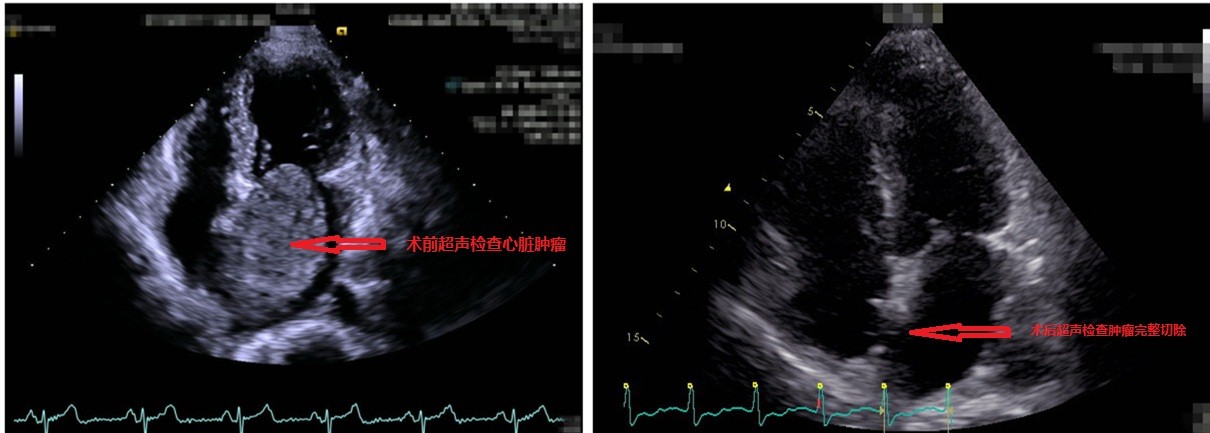

图为术前与术后心脏超声对比图

由于心脏内肿瘤体积大,患者随时可能出现急性心衰和猝死,应积极手术治疗。心脏外科与普外科联手确定了患者的诊疗方案:先由心脏外科团队切除心脏内肿瘤,患者恢复平稳,2-3周后再行乳腺癌切除手术。沈冬焱带领手术和体外循环团队,在麻醉科和手术室的配合下,应用全麻低温体外循环,由右心房切入,可见肿瘤生长于房间隔部位,大小基本占据了整个左心房,约7*5cm,完整切除肿瘤后,取自体心包片修复被切去的房间隔。心脏内肿瘤的病理结果最终证实了专家们的术前判断,为良性粘液瘤。